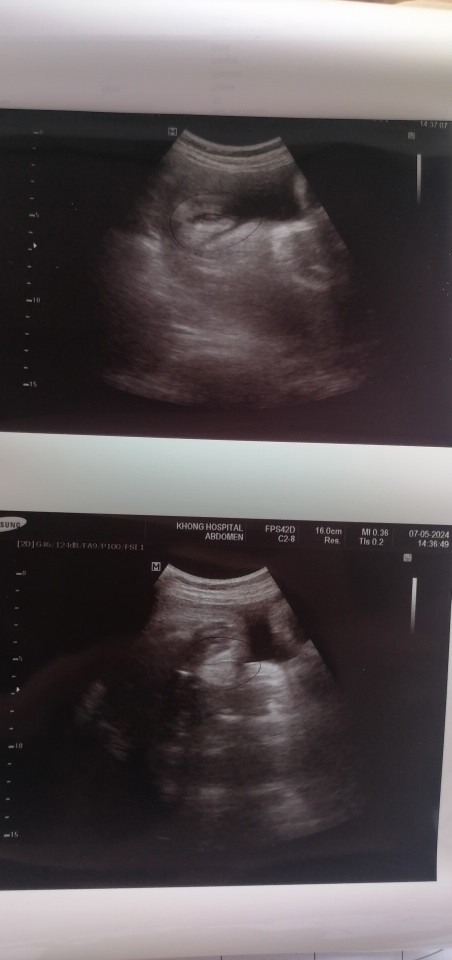

ภาพอัลตราซาวน์ ลูกสาว 37 week ใกล้เจอกันแล้วค่ะ

ต้าวคนที่2ขอให้หนูสมบูรณ์แข็งแรงนะคะ❤️👧🏻